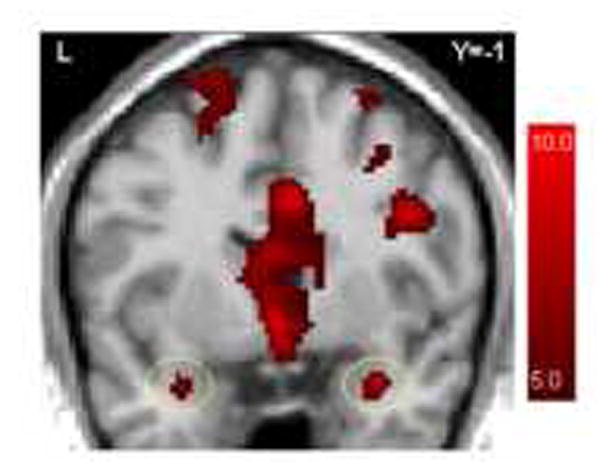

To investigate the effects of viewing high-arousal pictures immediately prior to responding to the cognitive control task, we analyzed the effects of picture arousal on brain regions recruited in response to the incongruent-arrow condition. The top of Figure 6 illustrates random effects contrast maps of responses to incongruent arrows trials preceded by high-arousal stimuli relative to incongruent-arrows trials preceded by low-arousal stimuli for neurotypical control (left) and autism (right) participants. This figure reveals that neurotypical participants recruited the lateral midfrontal cortex to a greater extent in response to the incongruent trials when preceded by arousing pictures. Each cluster of high-arousal > low-arousal activation in response to incongruent arrow trials for both diagnostic groups was localized and the anatomical label and Talairach coordinates are reported in Table 2.

Figure 6.

Top: Random effects contrasts (p < .01) comparing incongruent arrow trials preceded by high-arousal and low-arousal pictures for the neurotypical (left) and autism (right) groups. Bottom: Activation responses from voxels in the right midfrontal cortex denoted by the red crosshairs (Brodmann’s area 9) for the neurotypical (left) and autism (right) groups.

The bottom of Figure 6 illustrates the timecourses of average BOLD HDRs from the right mid-frontal cortex for these two conditions. To evaluate statistically the apparent group difference in differential response to incongruent arrow trials preceded by high-arousal and low-arousal pictures in the right lateral midfrontal cortex, we computed a Group × Arousal repeated-measures ANOVA on average amplitude activation values. These were derived by averaging BOLD activations at the peak of the HDR (i.e., 4.5 – 6.0 seconds after the onset of the incongruent arrows) in response to incongruent arrow stimuli preceded by arousing pictures and incongruent arrow stimuli preceded by unarousing pictures from voxels identified to be active in the neurotypical group by the random effects analysis described above. Because there was no statistically significant effect of arousal in the autism group in this region, and because all functional data were transformed to the same normalized space, to generate average HDR’s for the autism group we queried voxels showing an effect in the neurotypical group. The Group × Arousal repeated-measures ANOVA reveal a main effect of Arousal, multivariate F(1,30)=4.25, P<0.05, no main effect of Group, F(1,30)=0.60, P>0.40, and an Arousal × Group interaction, multivariate F(1,30)=4.18, P<0.05. This critical interaction indicates that the effect of viewing high-arousal pictures that immediately preceded incongruent arrows in a functionally-defined region of the right lateral midfrontal gyrus is greater in the neurotypical group than in the autism group. This was the only region that showed a significant Group × Arousal interaction on average amplitude activation values.

Findings also suggest the possibility that autism may be characterized by changes in latency to physiologic response in addition to differences in response magnitude, particularly in light of electrophysiological evidence that autism is characterized by delayed responses to certain classes of stimuli (e.g., Webb et al., 2006). Our epochal analysis strategy was based on an empirically-derived hemodynamic function (Kirino et al., 2000; McCarthy et al., 1997). However, the hemodynamic response functions depicted in Figure 6 are model-free; that is, once functional regions of interest had been derived, average timecourses were extracted that were not contingent on a particular response function. Visual inspection of Figure 6 suggests that the peak response to the incongruent condition proceeded by arousing stimuli may be slightly delayed in the autism group (i.e., between 4.5-6.0 seconds) relative to the control group (i.e., 4.5 seconds). However, the absolute magnitude of the peak response in the neurotypical group is relatively double the peak response in the autism group, indicating that amplitude differences between groups are a more robust effect in this context.